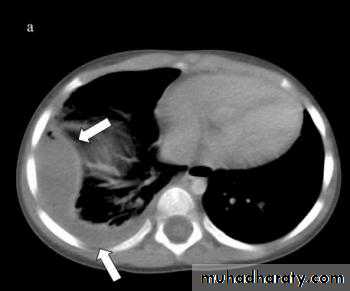

• 6-CT scan

CT san : clarify the diagnosis when the CXR is equivocal